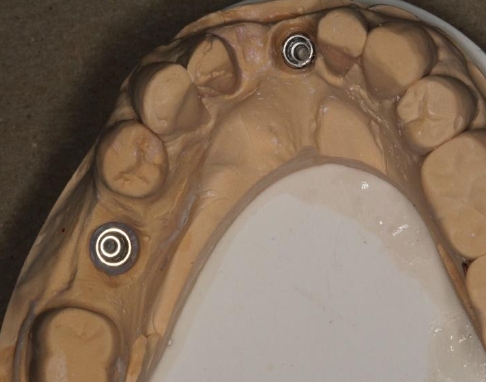

Some things to look for when inspecting the impression:

No voids

Impression coping is fully embedded in material

Include all important details

In the closed tray impression technique, how do you connect the impression coping to the analog?

Using the guide pin; then it is repositioned back into the impression

In the open tray impression technique, how do you connect the impression coping to the analog?

The impression coping is embedded in the VPS impression material; when connecting the analog to the impression coping, it is imperative to hold the analog with your fingers to prevent rotation of the coping